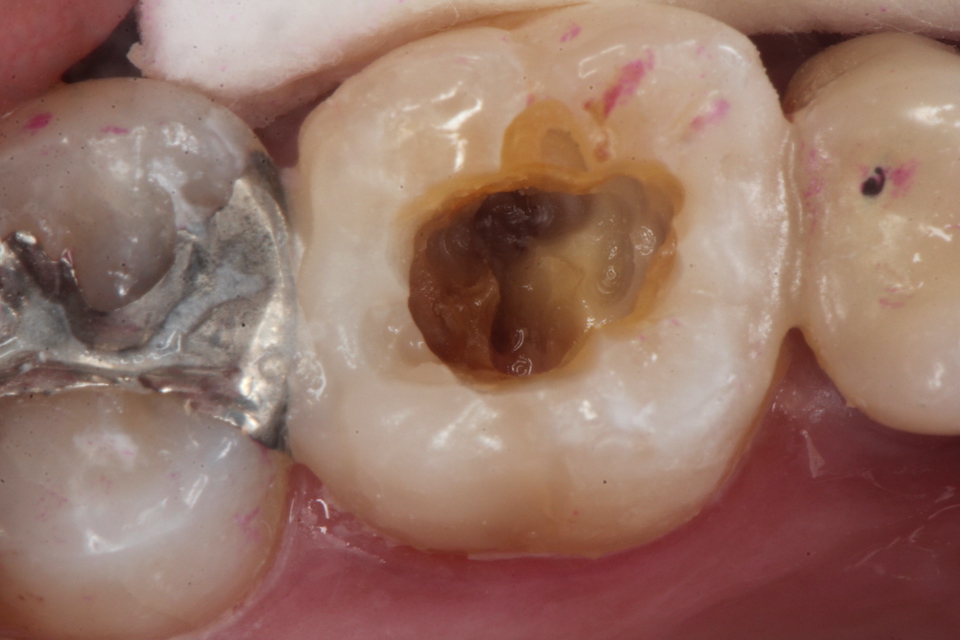

残根上のCR(ダイレクトボンディング)8 2025.11.12

ブリッジ脱離で2次カリエス+Perでグラグ… 2025.11.01

ブリッジ脱離で2次カリエス+Perでグラグ… 2025.10.31